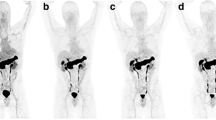

On delayed whole body imaging, there was intensely increased tracer binding in the pancreas in all patients as the gastrin-releasing peptide receptor (GRPR) is highly expressed in the pancreas in humans (Figs. 1 and 2). Mildly increased [99mTc]DB4 activity was noted in the gastrointestinal (GI) tract. In patient 6, the tracer excretion into the bowel increased over time and there was significant gut activity noticed at 3 h after injection.

[99mTc]DB4 imaging of Patient 3. a Whole body planar imaging at 1 h after injection shows increased uptake in the pancreas (arrowed) and low tracer excretion into the bowel but little uptake in bone lesions. b Spot views from SPECT/CT demonstrate increased [99mTc]DB4 uptake in the right proximal femur, c the left anterior pubic ramus and d in the lower lumbar spine.

Three of the six patients from group 2, however, did demonstrate increased [99mTc]DB4 binding in some bone lesions. Patient 1 had uptake in a right inferior pubic ramus lesion on both the dynamic and static lesion (best seen on SPEC/CT at 90 min). This lesion was also seen on CT and demonstrated uptake on bone scan. However, conventional imaging also revealed a lesion in the T12 vertebral body, which did not show [99mTc]DB4 uptake and also a small lesion seen in the left 5th rib on bone scan, which was also negative on [99mTc]DB4 uptake. Patient 3 had extensive bone metastatic disease in the central and axial skeleton on CT and bone scan (Fig. 1). Increased [99mTc]DB4 binding was demonstrated in lesions in the L5 vertebral body, the right proximal femur and in the left iliac crest (Fig. 2). It appeared that positive [99mTc]DB4 binding was associated with less sclerotic lesions. SPECT/CT at 90 min after tracer injection did show further foci of increased [99mTc]DB4 binding in metastatic deposits, but the majority of the extensive bone metastatic disease was not visualised. Positive foci on [99mTc]DB4 appeared to have progressed more on follow up bone scans than the negative lesions. In summary, extensive metastatic bone disease showed increased [99mTc]DB4 binding in only a few lesions. Patient 6 demonstrated bone metastases in the pelvis, sacrum, spine, ribs and in the left proximal femur on CT and bone scan. Focally increased [99mTc]DB4 binding was identified in only a left 6th rib lesion; otherwise, all other known bone metastases were negative. This patient also had multiple liver metastases which had decreased in size following previous therapy, with residual lesions seen on CT particularly in the left lobe of the liver. SPECT/CT showed increased [99mTc]DB4 binding in a liver metastasis in the left lobe of the liver. On CT, there was a small metastatic nodule in the lung. Follow-up CT showed progression of liver and lung lesions.